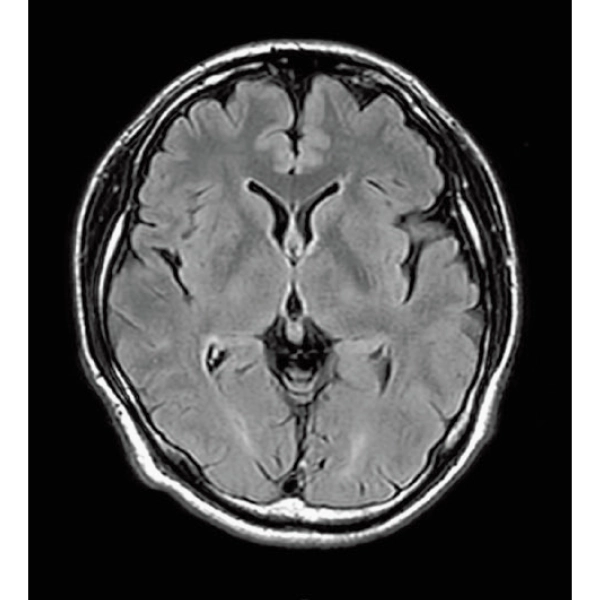

ShortScan

FLAIR, 1:14

DWI, 0:36

3DTOF MRA (MIP), 1:26

3D Balanced SARGE

with Phase Cycling,

0.93×0.70×1.0(0.5)mm, 1:44